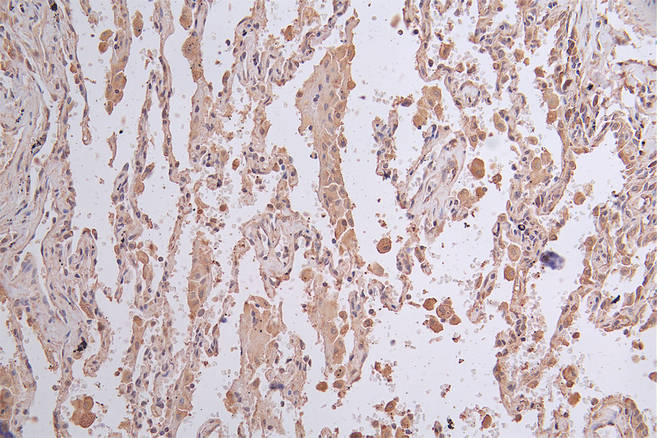

IHC image of CSB-RA156336A0HU diluted at 1:50 and staining in paraffin-embedded human lung cancer performed on a Leica BondTM system. After dewaxing and hydration, antigen retrieval was mediated by high pressure in a citrate buffer (pH 6.0). Section was blocked with 10% normal goat serum 30min at RT. Then primary antibody (1% BSA) was incubated at 4°C overnight. The primary is detected by a Goat anti-rabbit polymer IgG labeled by HRP and visualized using 0.26% DAB.

產品描述:CSB-RA156336A0HU LGR6重組單克隆抗體是經過嚴格驗證的高特異性科研工具,靶向LGR6(Leucine-rich repeat-containing G-protein coupled receptor 6),該蛋白屬于G蛋白偶聯受體家族成員,在干細胞調控及組織再生中發揮重要作用,尤其與表皮干細胞分化、毛囊發育及腫瘤發生相關。本抗體通過ELISA實驗驗證可特異性識別天然及重組LGR6蛋白,免疫組化(IHC)實驗顯示其在石蠟包埋組織中能清晰定位細胞膜表達,免疫熒光(IF)染色呈現高分辨率的亞細胞定位信號,流式細胞術(FC)進一步證實其適用于活細胞表面抗原檢測。推薦工作濃度為IHC/IF/FC 1:50-1:200,可滿足多樣本類型的實驗需求。該產品適用于干細胞生物學、組織再生機制研究、腫瘤微環境分析及發育生物學等領域,尤其為探索LGR6在表皮穩態維持、癌癥干細胞標志物篩選等方向提供可靠檢測工具。本產品僅供科學研究使用,需根據實驗體系優化具體條件。

應用范圍:ELISA, IHC, IF, FC

Application Recommended Dilution IHC 1:50-1:200 IF 1:50-1:200 FC 1:50-1:200 -